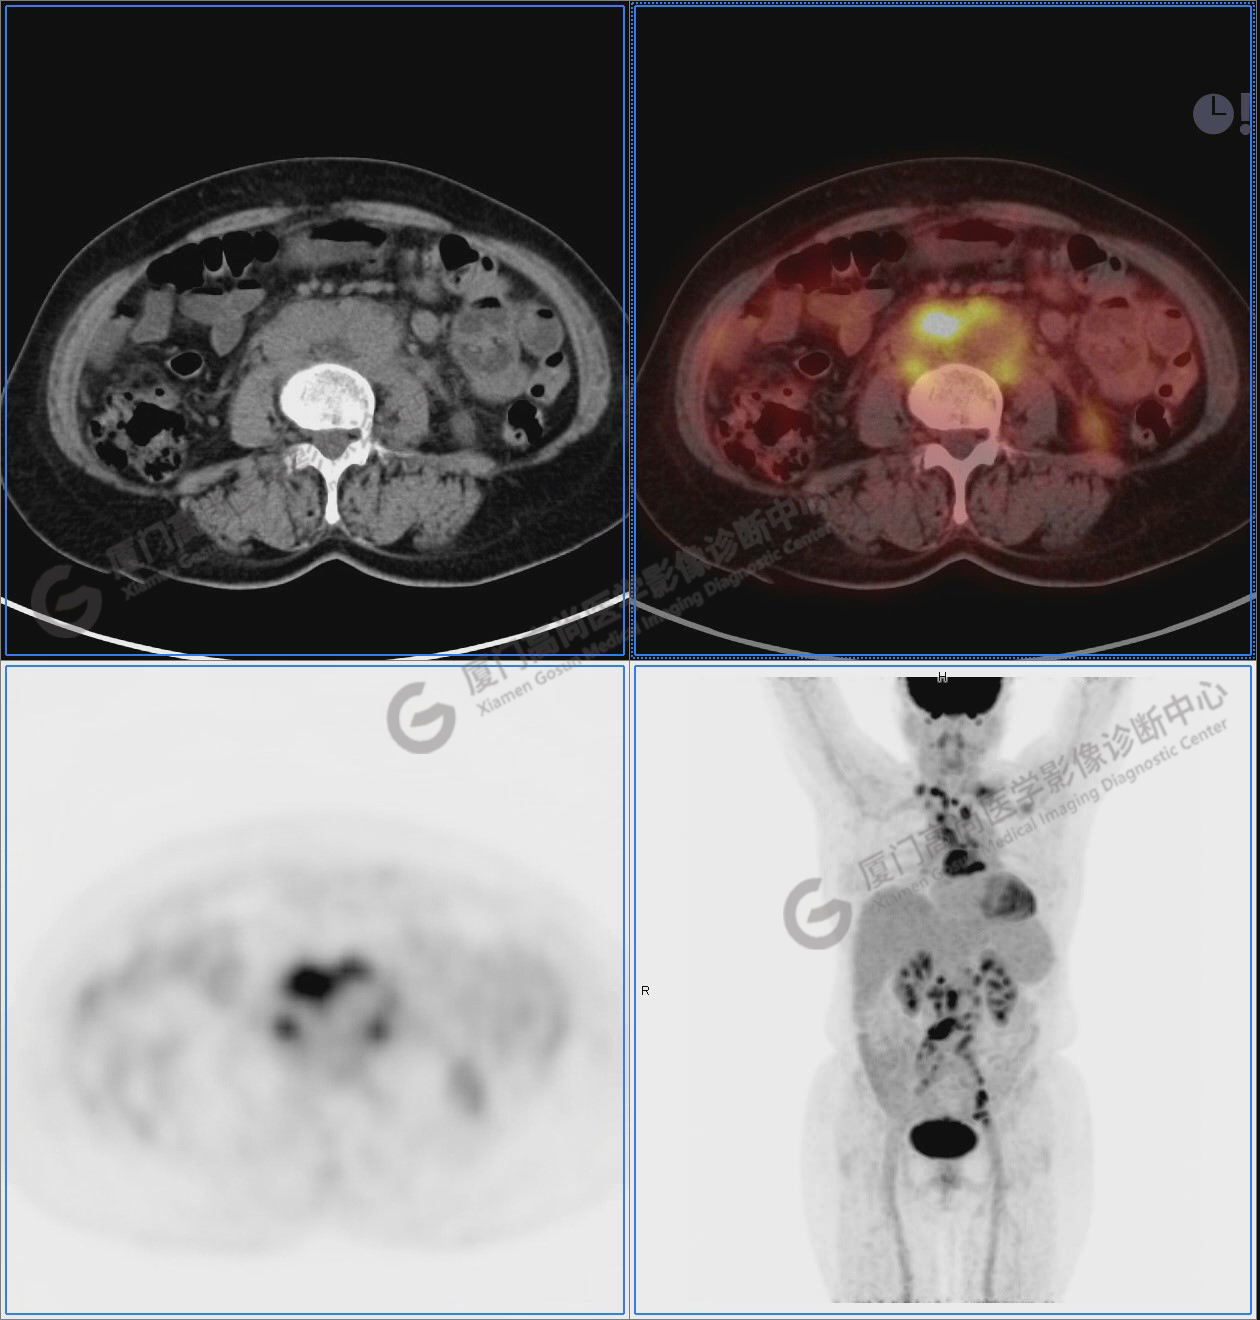

圖1:PET/CT全身圖像

圖2-9:雙側(cè)鎖骨區(qū)、縱隔、右側(cè)內(nèi)乳區(qū)、腸系膜緣、腹膜后、雙側(cè)髂血管旁及盆腔多發(fā)腫大淋巴結(jié)影,代謝不同程度增高,考慮為轉(zhuǎn)移。

圖8

圖9